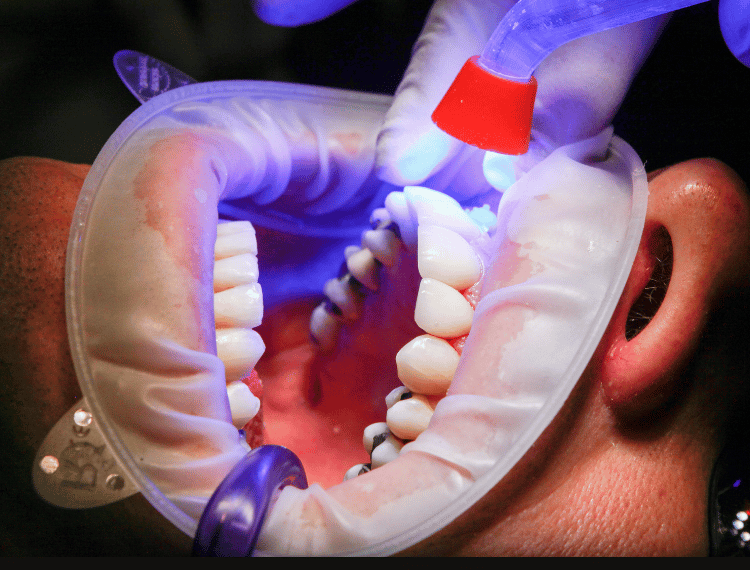

إزالة التصبغات والجير وتحسين لون الأسنان بطرق آمنة ونتائج فورية.

توفر الجودة والراحة مع التكنولوجيا المتقدمة والتعقيم للحفاظ على صحة أسنانك.